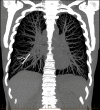

Contraceptive implant migration into the pulmonary circulation is an uncommon, but potentially serious complication. We describe an "aspiration" technique for percutaneous retrieval of a contraceptive implant from a subsegmental pulmonary artery, using a Penumbra Neuron MAX 088 guiding catheter and a Merit Medical VacLok Vacuum Pressure Syringe, as an alternative to the previously described snare technique. Our patient had an uneventful recovery and was discharged home on the same day.